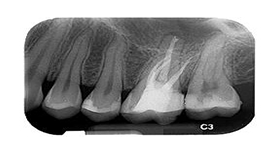

When a tooth becomes infected or damaged, root canal treatment is often the only way to save your tooth and repair the damage. Infection spreads to the bone and tissues and an abscess forms at the roots.

The treatment involves clearing the infection after numbing the tooth by a cleaning and disinfecting process of the roots. The root canals are then filled with an inert material and sealed. A crown has to be placed following the treatment to protect the tooth from further damage.